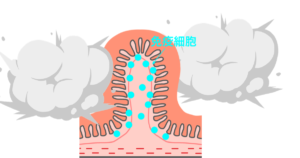

腸の壁は、絨毛と呼ばれる多くの突起物に覆われ、その中に免疫細胞があります。細菌やウィルスがやってくると免疫細胞がやっつけてくれます。NK細胞はがん細胞を食べちゃう細胞です。

私たちの腸には免疫細胞(マクロファージ、Tレグ細胞、Bリンパ球、NK細胞)がありますが、暴走してしまうことがあります。これが本当に始末に悪いんですね〜。味方まで攻撃して手に追えなくなってしまいます。

免疫細胞 暴走とブレーキ

暴走するまでの流れ

脳を襲うこともある。